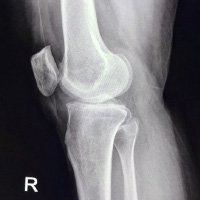

加齢に伴い膝の軟骨が摩耗してくることで関節炎を起こし痛みが出てくる疾患です。

初期は立ち上がりや歩き出し、動き出しの痛みで発症します。膝に水が溜まる場合も多いです。

運動器疾患(怪我、慢性疾患)の検査といえば、単純X線検査(レントゲン検査)が第一選択となり、骨や関節の形態を診て診断する際には非常に重要な検査です。同時に、レントゲン検査では写らない部位の画像診断にはエコーが非常に有用です。当院では運動器エコー診療を積極的に活用して患者さんの早期診断、早期治療に活かしています。